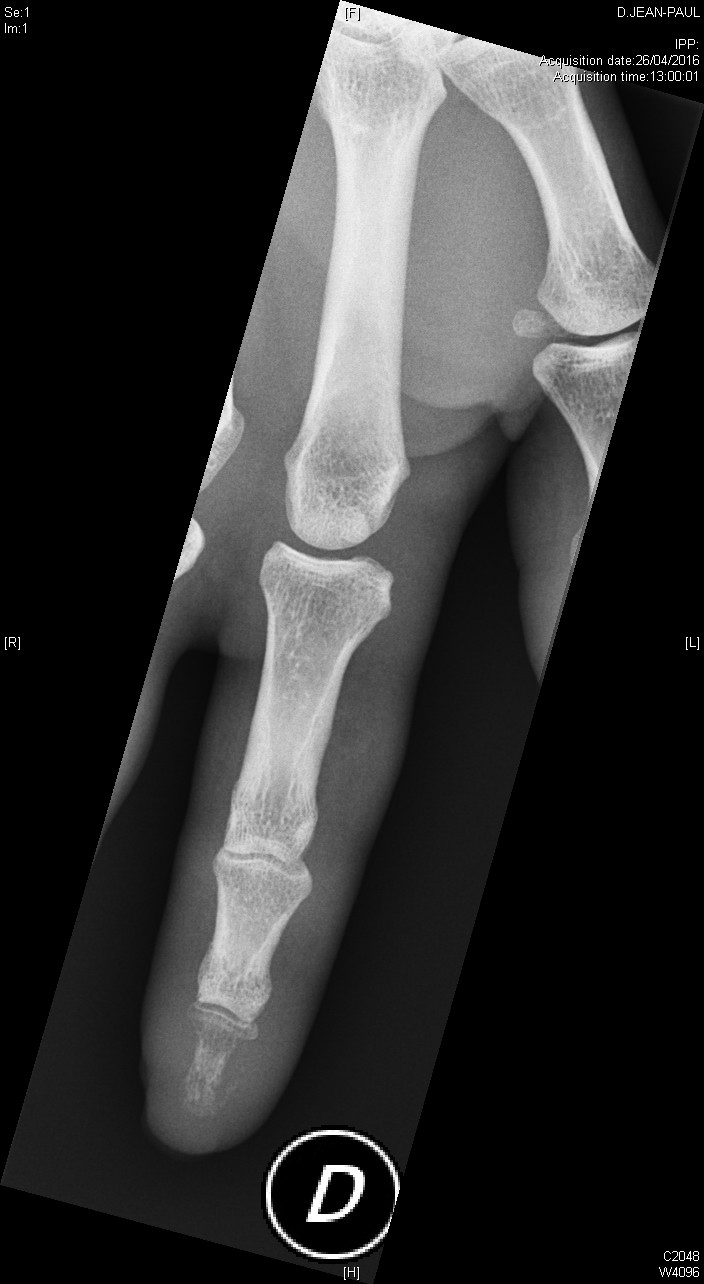

Ostéite de la phalangette